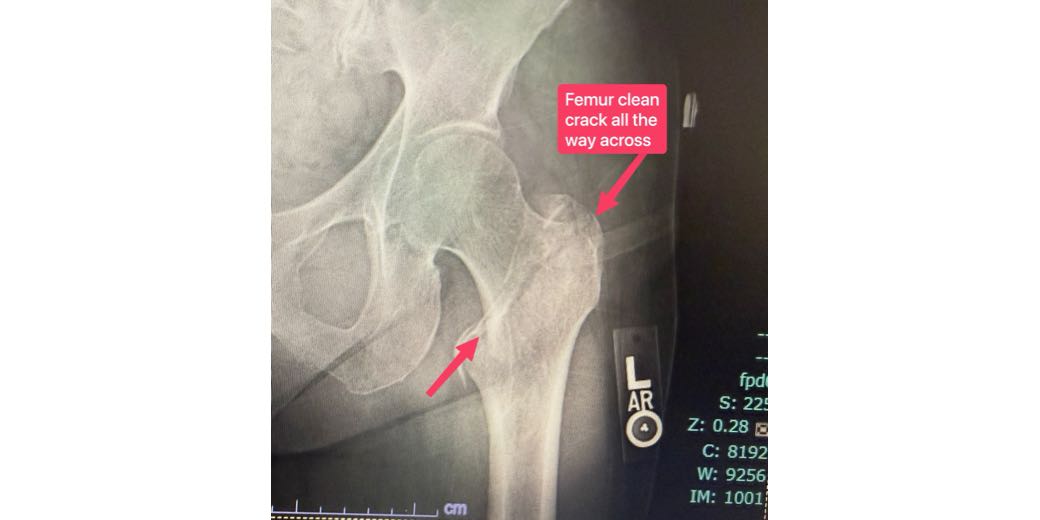

It’s Still a Slider — The Broken Femur Edition

It’s a SLIDER, not a button! You may remember last June when I published a PSA entitled, “PSA — SOS Button for Apple Watch Fall Detection is a SLIDER!” I posted that after I had a hard fall while walking Kepler, which caused me to break my nose. After years of looking at the SOS […]